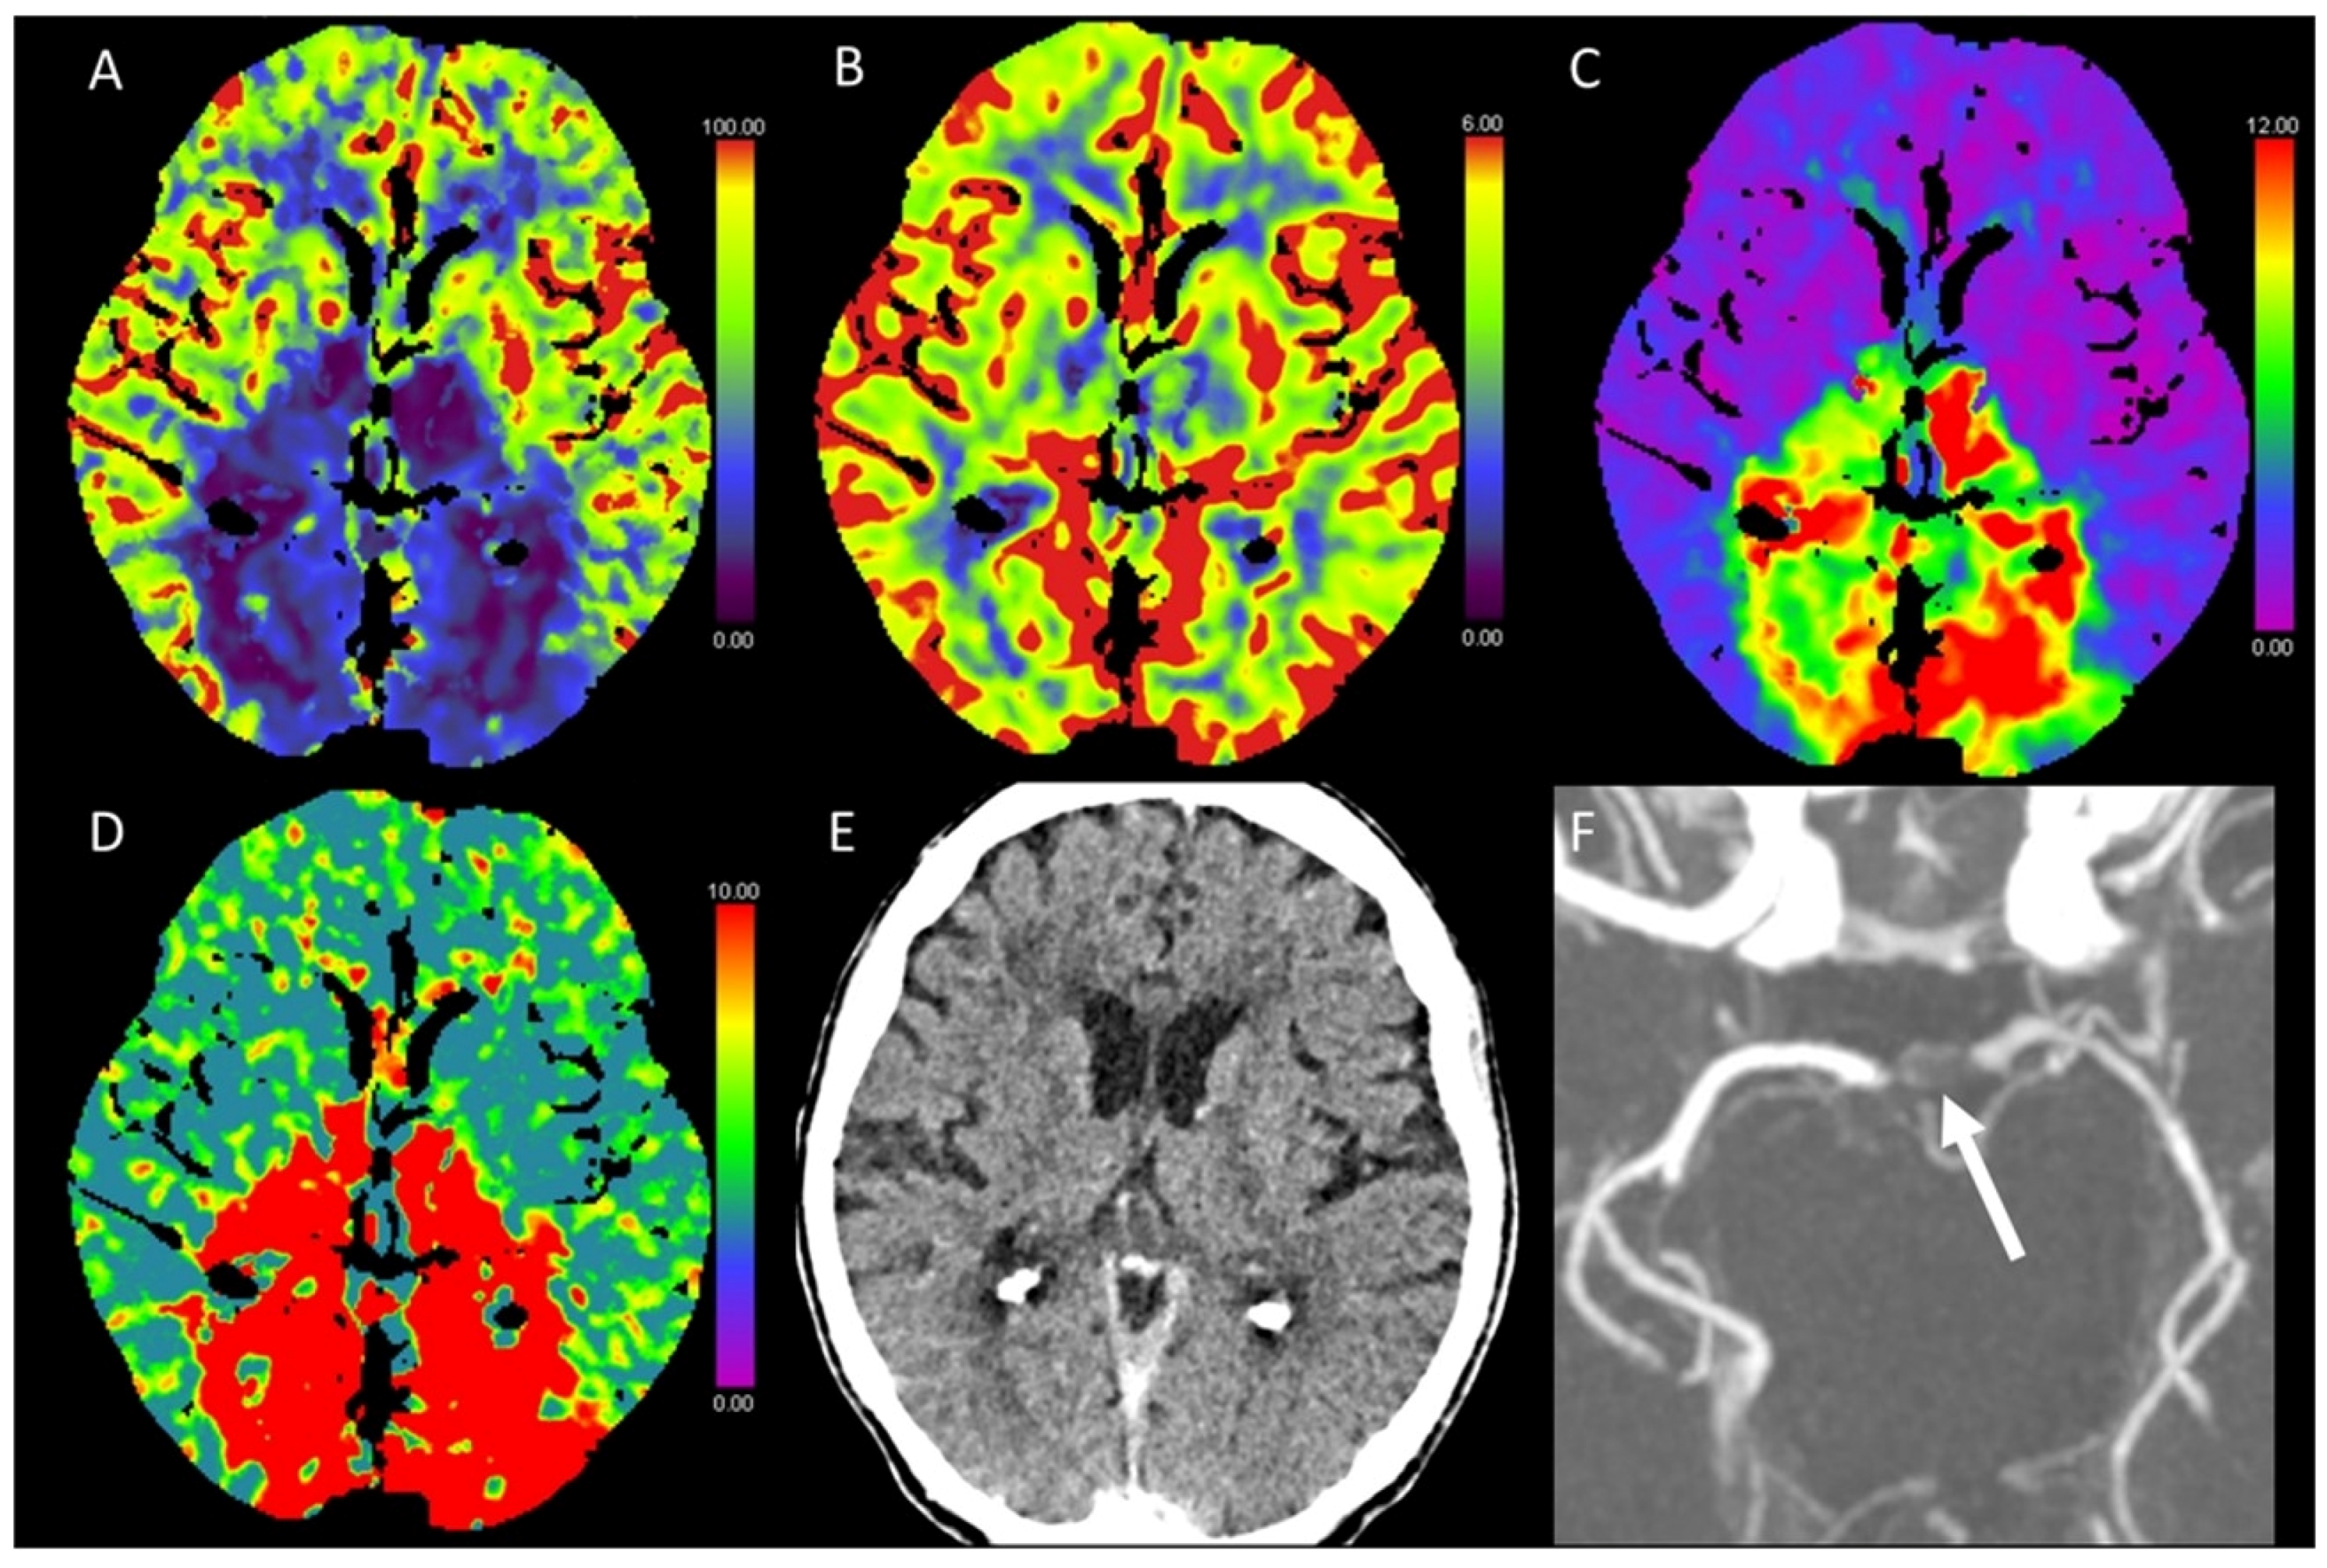

3.6. Vasospasm

3.7. Migraine